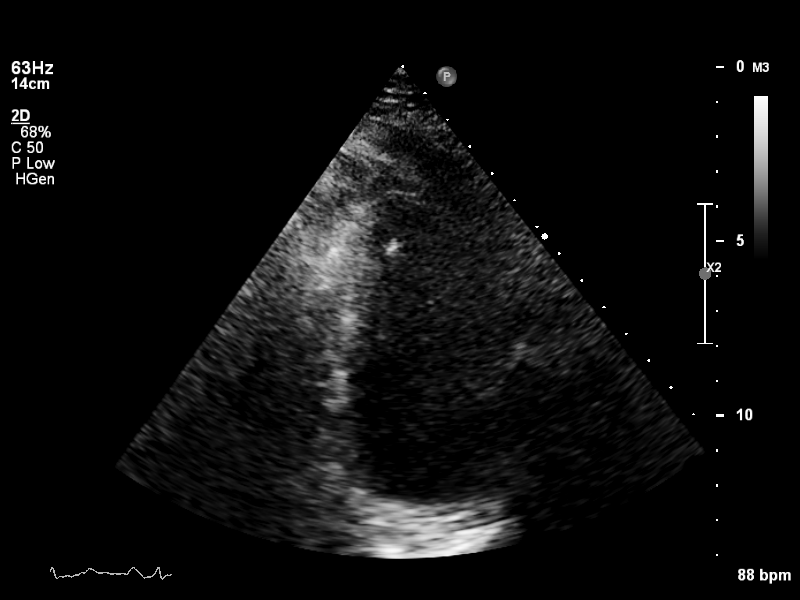

a4ch-full a4ch-full Apical 4-chamber showing the full depth of all four chambers (no LV/RV focus)